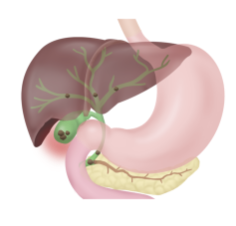

- 담낭, 췌장, 간, 비장, 신장 등의 종양: 복부 CT는 위장관 종양 및 다른 내장의 종양을 확인하는 데 유용합니다. 담낭, 췌장, 간, 비장, 신장 등 다양한 내장의 종양이 존재할 수 있으며, 복부 CT를 통해 종양의 위치와 크기를 파악할 수 있습니다.

- 담낭염: 복부 CT는 담낭의 염증을 확인하는 데 유용합니다. 담낭염은 담석, 감염, 알코올 소비 등이 원인이 될 수 있으며, 복부 CT를 통해 담낭염의 정도를 확인할 수 있습니다.